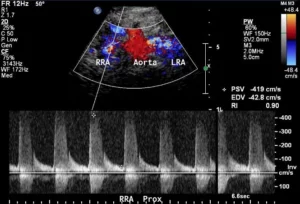

The most common way to diagnose RAS with DUS is with reliance on PSV within the renal artery as well as the ratio of the PSV as measured in the aorta at the level of the renal artery origin and the PSV at the level of the superior mesenteric artery. This is the renal:aortic ratio (RAR). The renal aortic ratio cannot be used when significant aortic disease is present or when aortic flow velocity is greater than 100 cm/sec or less than 40 cm/sec. A parvus et tardus waveform in the distal main renal artery or parenchymal branches also suggests a proximal stenosis.

Renal artery duplex ultrasound criteria for renal artery stenosis have been validated by comparing duplex measurements to contrast angiographic assessment of narrowing. Generally, these comparisons have shown renal artery duplex ultrasound to have excellent clinical utility with sensitivity and specificity usually reported to be well above 80%. The criteria that are most commonly used in clinical practice have been derived from a prospective, blinded study, in which 102 patients who were clinically suspected of having renal artery stenosis underwent both renal artery duplex ultrasonography and contrast angiography. Using a cutoff peak systolic velocity of 200 cm/sec or a renal aortic ratio of 3.5, resulted in sensitivity of 98%; specificity 99%; positive predictive value 99%; and negative predictive value 97%.

The renal resistive index is another measure obtained during a complete renal artery duplex ultrasound. The resistive index is calculated from peak systolic velocity and peak end-diastolic velocity obtained in branches of the renal artery at the level of the medulla. It is measured in both the superior and inferior poles of the kidney. The resistive index is calculated by the following equation: (1-EDV/PSV)*100. A lower resistive index will theoretically suggest a less resistive parenchyma and a healthier kidney. Also, according to one study, a resistive index < 0.8 may suggest better clinical outcomes following renal revascularization, although more recent publications have not repeated this finding. This may be because the resistive index has questionable reliability. Small measurement errors can result in significant changes in the calculated renal resistive index. Also, conditions other than renal artery disease may affect the renal resistive index. Examples include obstructive uropathy, hypotension, bradycardia and a peri-nephric fluid collection. The renal resistive index may have more utility in surveillance of transplant kidneys.